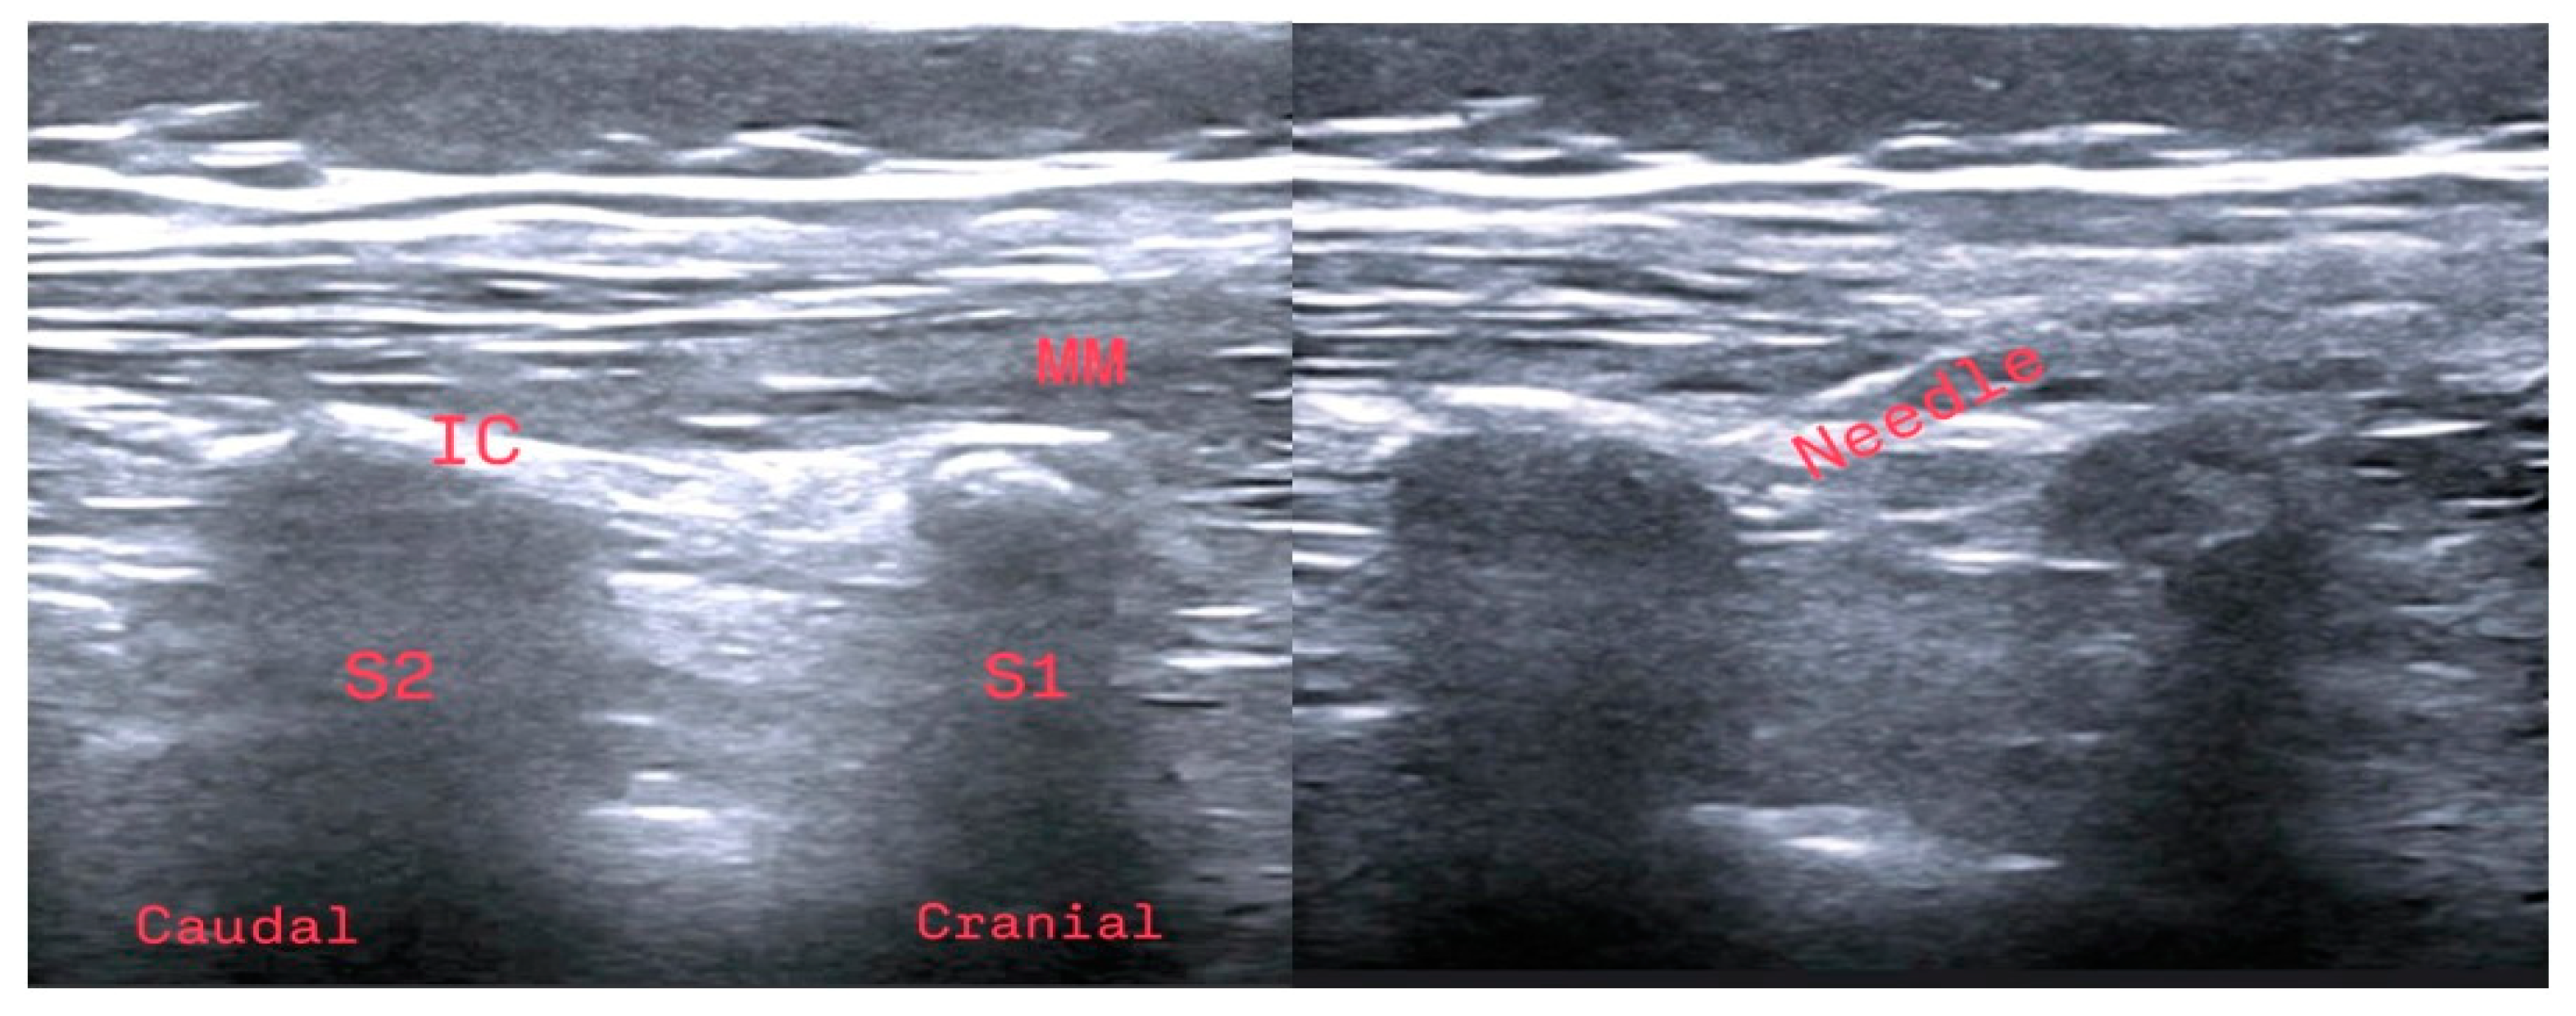

2.4.1. Ultrasound-Guided Sacral Erector Spinae Plane Block

When Group S patients were under general anesthesia and before beginning surgery, they were positioned on the lateral side. Aseptic conditions were ensured for the block, and a linear ultrasound (US) probe (MyLab™ Five; Esaote Europe BV, Maastricht, The Netherlands) was placed on the L5 vertebra spinous process in the sagittal plane to identify the starting point of the sacrum. The probe was moved caudally to visualize the sacral medial crest. Continuing in the lateral direction, the probe was used to locate the intermediate sacral crest. After obtaining an optimal US image at the S2 level, a block needle (50 mm, 21G short bevel) (Stimuplex A, B. Braun, Germany) was advanced craniocaudally until bone contact was achieved. Before LA injection, the needle was aspirated to exclude inadvertent intravascular placement of the tip. Marcaine (0.25%; 0.5 mL/kg; maximum 10 mL) was injected between the multifidus muscle and the intermediate sacral crest. The same block procedure was repeated on the patient’s other side (Figure 1).

Figure 1. Anatomical representation of the sacral erector spinae plane block under ultrasound guidance. IC: intermediate crest; MM: multifidus muscle; S1: first sacral vertebra; S2: second sacral vertebra. The sacral erector spinae plane block application.